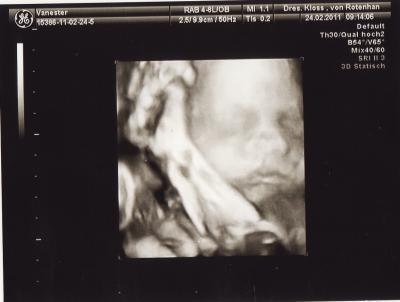

Soo nun kann ich mein kleinen auch endlich mal sehen wie er aussieht.. und er ist so süß.. sieht genauso aus wie mein großer nur leider habe ich bei mein großen nur 1 bildchen, weil er sich nicht zeigen wollte.. Naja bei diesen Baby ist es nicht anders aber naja seht selbst.. Denke es gibt besser 3D Bilder aber dafür das er auch fotoscheu ist sind die ganz niedliche geworden.. Achso und statt 75euro bezahle ich nur 50 euro.. Lg Britta

Bild zu Soo 3D bilder abgeholt... - Forum für April - Mamis